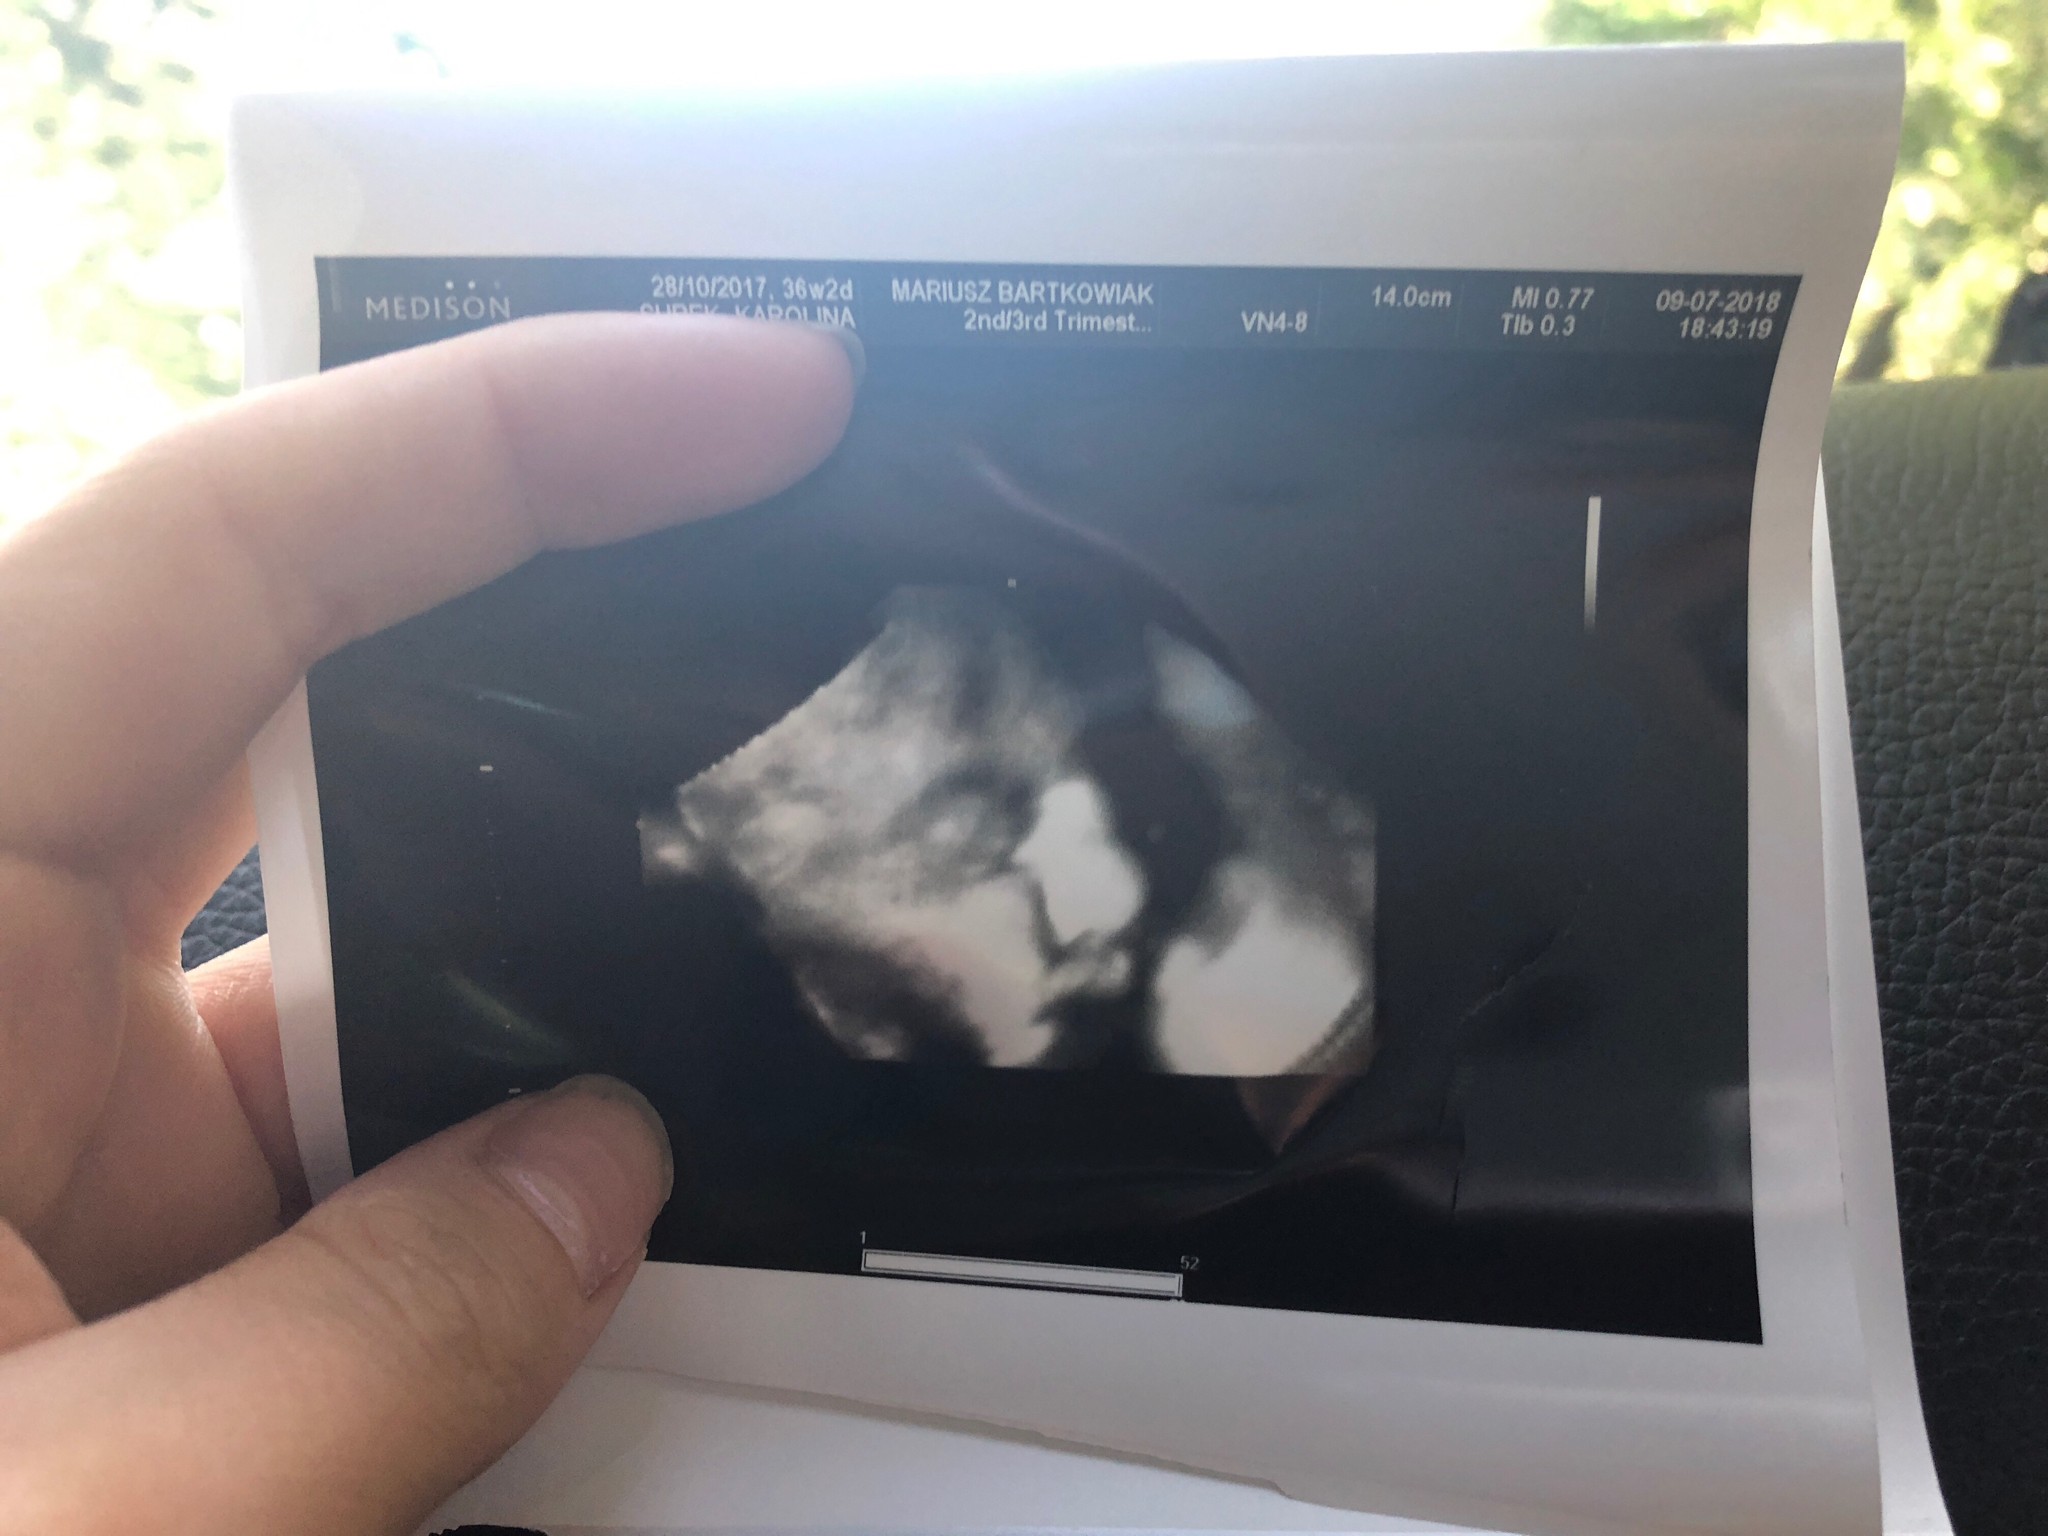

Mała wazy już 2,8 kg także przez 2 tyg przybrała 400 g. Leży nadal główka w dół. Pokazała buźkę na usg, z takiej dziwnej strony i śmiesznie wyglada, ale zawsze coś :)

Zobacz załącznik 875488